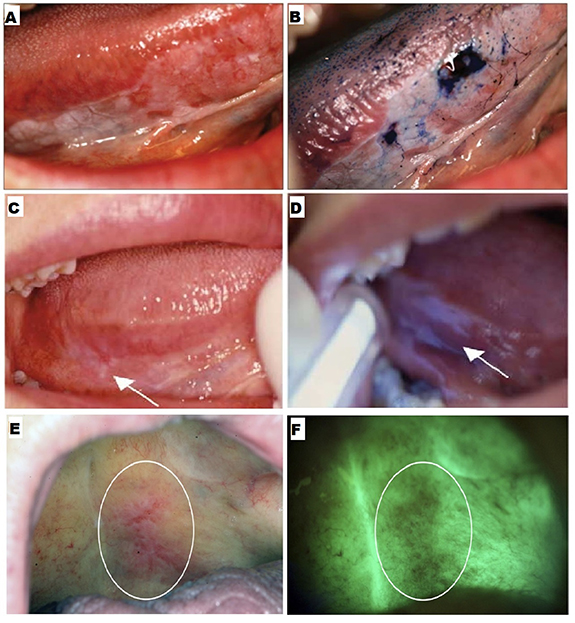

Vital staining involves using a dye, such as toluidine blue (TB) or tolonium chloride, to stain and highlight abnormal tissue regions. TB is a blue metachromatic dye that binds to nucleic acids. The nucleic acid content of dysplastic and anaplastic cells is higher as compared to normal cells. TB stains abnormal more than normal cells (figures 2(A) and (B)), which helps identify any mucosal changes. Additionally, intracellular canals are comparatively wider in the malignant epithelium, allowing greater penetration and more retention of the dye in abnormal cells [88]. The extent of staining depends on the degree of epithelial surface involvement, i.e. benign lesions show faint coloration, whereas dysplastic lesions and carcinomas show intense coloration. Vital staining can be used for screening asymptomatic patients.

Figure 2. Adjunctive aids. (A) An erythroplakia lesion on the right lateral border of the tongue, and (B) the same lesion viewed after toluidine blue staining. Reproduced from [10]. CC-BY-NC-ND 3.0. Copyright © 2013, The Author(s). (C) Clinically non-evident lesion in right lateral posterior tongue, and (D) the same lesion identified by Vizilite with irregular bluish-white reflection. Reprinted from [99], © 2004 International Association of Oral and Maxillofacial Surgeons. Published by Elsevier Inc. All rights reserved. (E) An erythroleukoplakia viewed under visible light and (F) the same lesion with autofluorescence. Reprinted from [102], © 2011 Mosby, Inc. Published by Elsevier Inc. All rights reserved.

Standard image High-resolution imageThe diagnostic efficacy of TB staining has been investigated in several studies. Lingen et al noted that the sensitivity and specificity of TB staining reported previously ranged 78%–100% and 31%–100%, respectively [6]. Rosenberg et al reported sensitivity values ranging from 93.5% to 97.8% and specificity ranging from 73.3% to 92.9% [89]. However, high false positive results were observed. Upadhyay et al reported a false positive value of 32.6%, due to to hyperkeratosis, hyperplasia, lichen planus, and traumatic ulcers [90]. A false negative value of 26.1% was primarily because of mild dysplasia [90]. Despite variability in the reported diagnostic efficacy of TB staining, it is considered an important adjunct to COE. It is recommended that any lesion with a positive TB stain should be considered for biopsy [91].

Chemiluminescence is the emission of visible light following a chemical reaction. Chemiluminescent techniques, such as those used in the product Vizilite®, have been devised to detect oral cancer at the early stages [98]. The patient's mouth is rinsed with 1% acetic acid solution to enhance light penetration, removing debris and disrupting the glycoprotein barrier. Vizilite® contains hydrogen peroxide and acetyl salicylic acid, which react and emit diffuse bluish-white light with a wavelength between 430 and 580 nm for approximately 10 min [99]. Dysplastic and neoplastic cells with abnormal nuclei reflect this light because of a high nucleus-cytoplasm ratio. Abnormal squamous epithelium tissue appears aceto-white, whereas normal epithelium appears darker (figures 2(C) and (D)) [98]. Vizilite® can serve as a tool for screening asymptomatic patients.

Several limitations are associated with the use of this technique. Although Vizilite® has been reported to have high sensitivity ranging from 77% to 100%, its specificity ranges from 0% to 27% [3, 99, 100]. In a study by Farah et al, ViziLite improved the visualization of lesions in high-risk populations [100]. However, it could not differentiate between benign, inflammatory, potentially malignant, and cancerous mucosal conditions. Mehrotra et al reported that Vizilite was ineffective in detecting dysplasia or malignant cells [101]. Although the lesions previously identified by standard light were enhanced by up to 60%, no additional lesions were detected.

Native fluorophores in the oral epithelium and submucosa can be excited upon exposure to light in the UV-visible range, causing the tissue to fluoresce [102]. Carcinogenesis induces modifications in their concentration and fluorescence properties. Autofluorescence imaging and spectroscopy have been used to analyze tissue autofluorescence. VELscope® is a commercial device that uses tissue autofluorescence for screening oral precancerous lesions based on the structural and metabolic changes of the epithelium and connective tissue upon interaction with light. When stimulated with intense blue light (400–460 nm), normal oral mucosa appears pale green (figures 2(E) and (F)) [88, 92]. Conversely, dysplastic and malignant lesions appear relatively darker because of reduced autofluorescence, which can serve to screen asymptomatic patients.

The reported sensitivity of VELscope® for identifying malignant and dysplastic lesions ranges from 50% to 100% [101–103]. A disadvantage of this technique is its relatively low specificity (15%–80%) [101–103]. Ford and Farah concluded that this technique is unreliable in diagnosing dysplasia without any clinical interpretation [104]. In another study, VELscope® effectively determined oral leukoplakias and erythroplakia, but it could not distinguish between dysplastic and benign lesions [103].